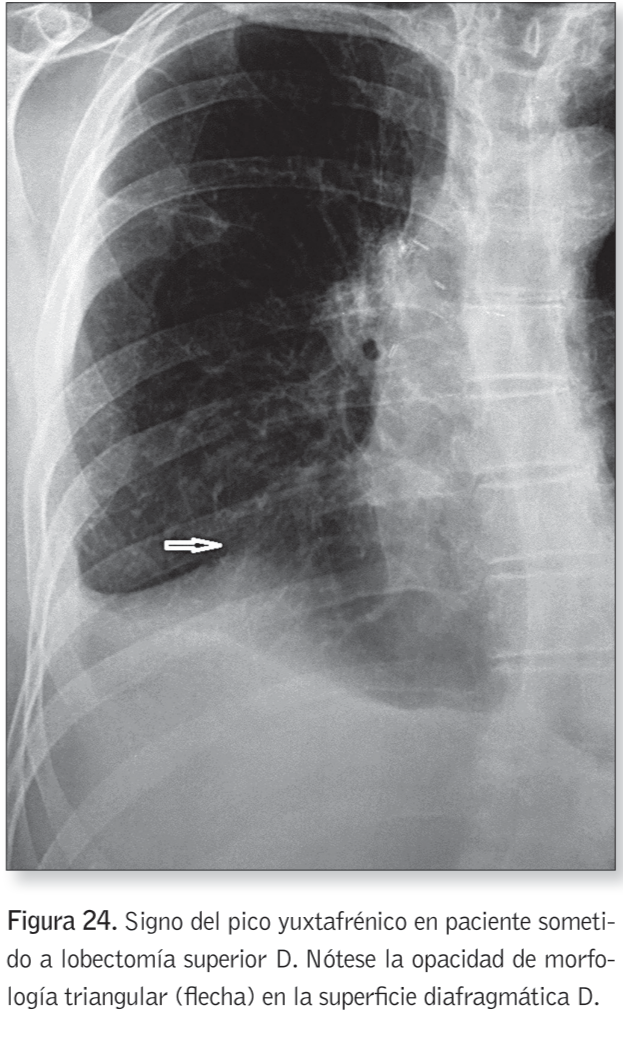

Signo del pico yuxtafrénico